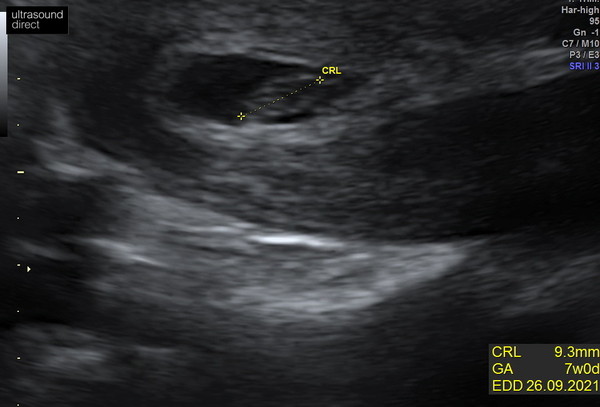

@mumof23188 hey, I’m doing really well so far. Still minimal symptoms but my latest scan was today, measured exactly 7 weeks which is exactly where I thought I should be. Lovely strong heartbeat again and was the first scan that my oh has attended so that was nice. How are you doing?

Moominmiss · 07/02/2021 15:06

This is today’s scan. She did an abdominal scan which I was a little disappointed with because I know a tv scan would have given us a clearer image. But was still amazing. We got sent loads of images from the scan and a few videos where we can see the heart beat flickering away ☺️